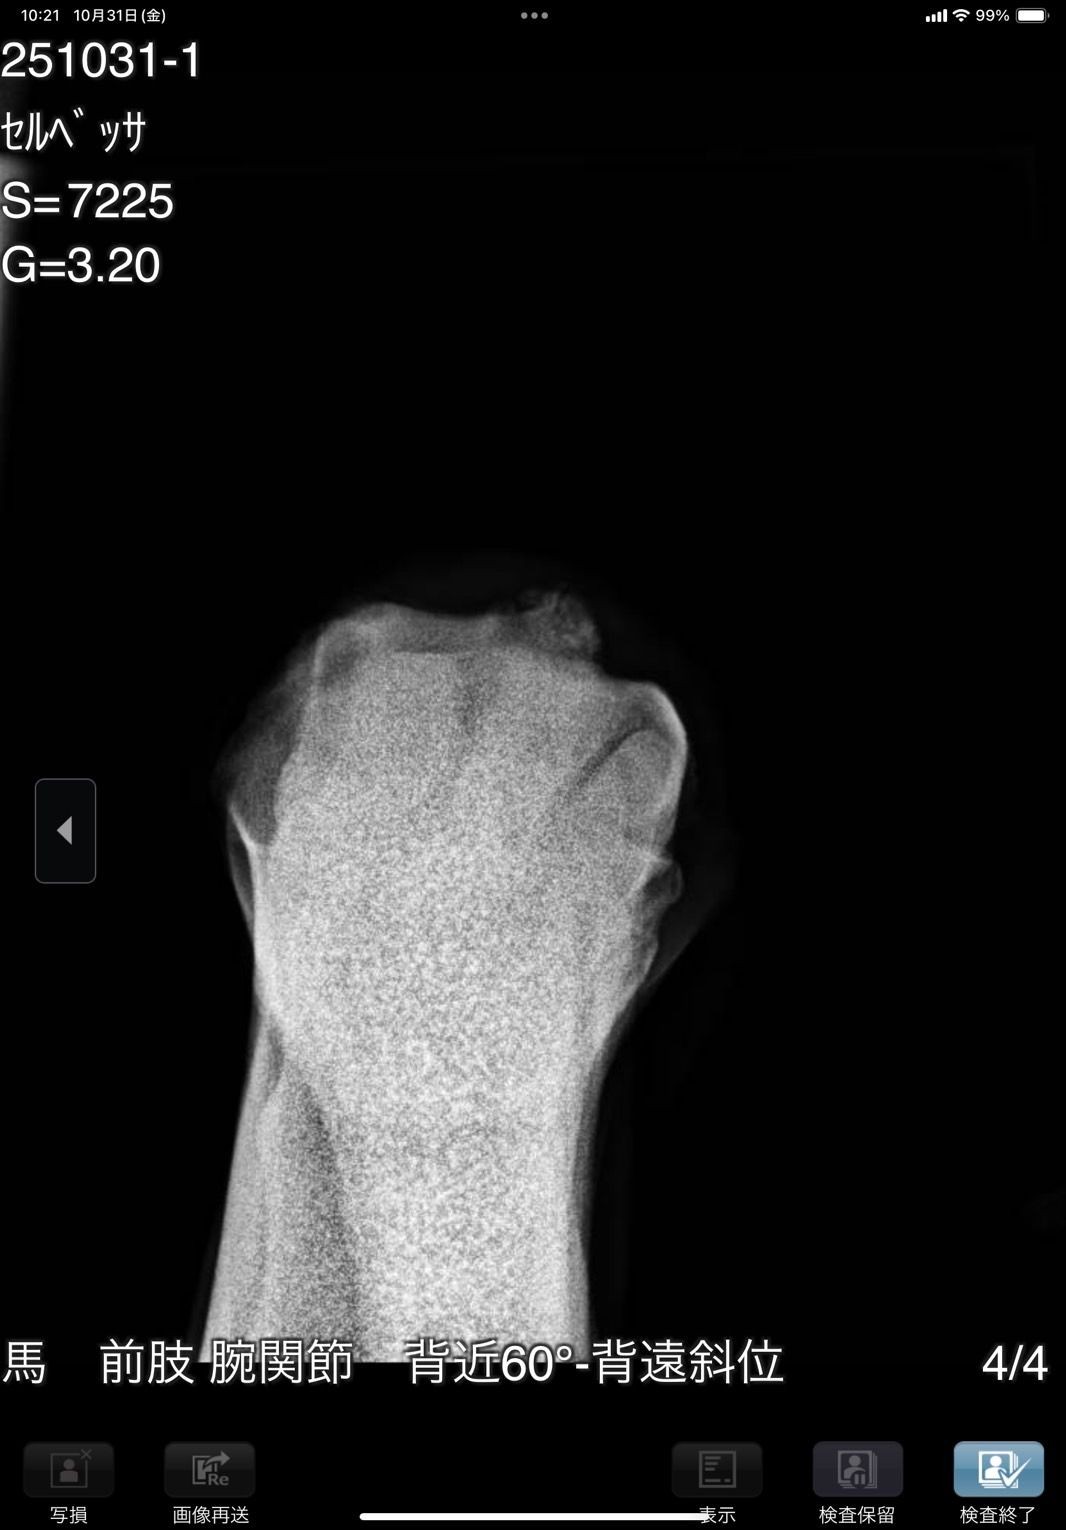

前肢が外向しているためか1歳秋の育成段階で右前に骨瘤ができ、中々固まらずに育成も遅れ、デビューは3歳4月となりました。デビュー後は4ヶ月で6戦を消化し比較的順調に出走できましたが、8/28の出走後にC3級への降級を狙って休養へ。帰厩に向けて乗りこんでいる所でしたが、10/31の調教後に右前膝に違和感があり、レントゲン検査を実施した所、骨片の剥離が見られました。その段階では大きな跛行は見られなかったためしばらく様子を見ましたが、速い調教を行うと歩様に違和感が出るため、手術が必要と考えられます。骨片除去手術を行いますと一定期間の休養が必要となるため、この度オークションへの出品とさせて頂きました。骨片除去手術は必要になると思いますが、元々の戦績からすると園田C2級で勝ち負け出来る能力があり、休養中にC3級への降級となりますので、適切な治療と休養をして頂ければ勝負になる可能性は高いと思います。骨折の状況については8/31撮影のレントゲン画像をご確認ください。

※10月31日の調教後に右前膝に違和感があり、レントゲン検査を行った所、骨片の剥離が見られました。